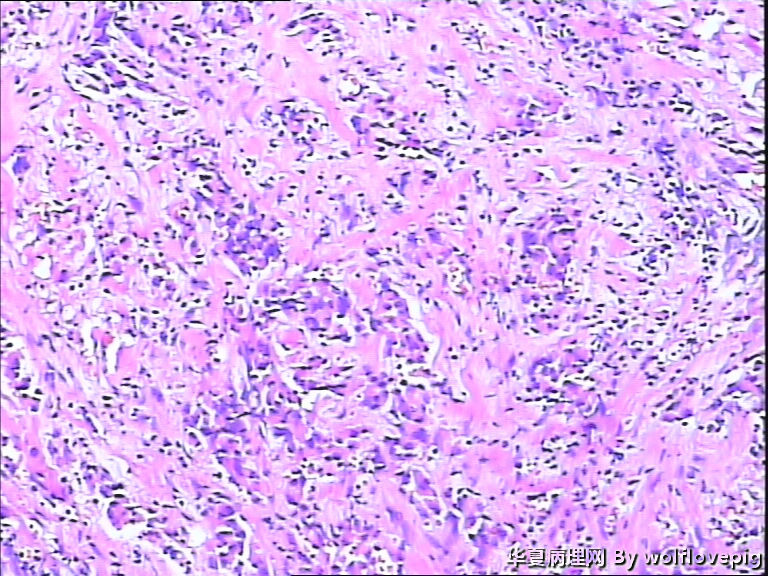

女,60y,发现右乳包块6+月。

灰白不整形组织一块:3*2*1.5cm,切面有一灰白区域,边界欠清,质韧。

标签:乳腺浸润性癌

浸润性癌。

浸润性导管癌,最好标记肌上皮。

浸润性导管癌

浸润性导管癌,分化差,除外混合癌(导管癌+小叶癌),免疫组化证实。(本例图像很多,局部炎症反应重,瘤细胞还成合体样无腺管形成似髓样癌,局部似炎性乳癌,局部似小叶癌,呵呵)